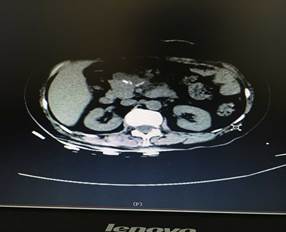

充分術(shù)前準(zhǔn)備后,在肝膽外科團(tuán)隊努力及麻醉科的鼎力支持下,歷經(jīng)4個多小時,大家成功在腹腔鏡下為患者進(jìn)行了胰腺巨大腫瘤及胰腺體尾端切除,脾臟、膽囊切除手術(shù)。術(shù)后第四天患者便進(jìn)食流汁,下床活動,復(fù)查情況良好(圖2、圖3),患者和家屬臉上都露出了久違的笑容。

圖2

圖3